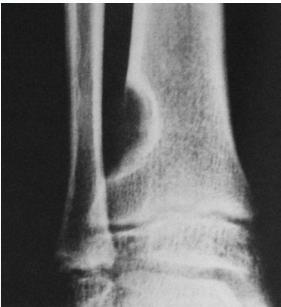

Aneurysmal Bone Cyst

- Child - young adult

- Metaphysis of long bone

- X-ray:

- Well-defined cyst

- Trabeculated

- Eccentrically placed

- Ballooning

- Bloody content

- Treatment:

- Curettage and bone graft

- Metaphysis, Eccentric